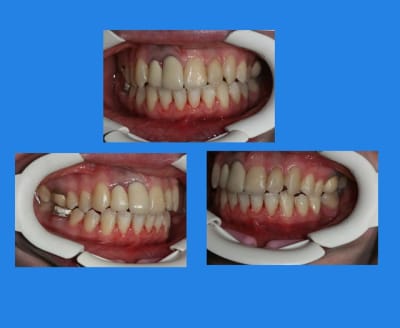

Voici le cas il y a un an

Elle était enceinte de 8 mois,

la voiture lui était déconseillée par son médecin,

j’ai donc décidé, avec l’accord de la patiente, de déposer (sans contention), car je ne voulais plus la laisser sans surveillance avec un matériel ortho en place

@+ Bjc.